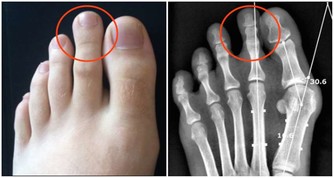

2、加陳醋:促進血液循環、緩解關節疼痛

生薑泡醋,能夠促進血液循環、增加抵抗力、緩解感冒,還有輔助治療關節炎的作用。